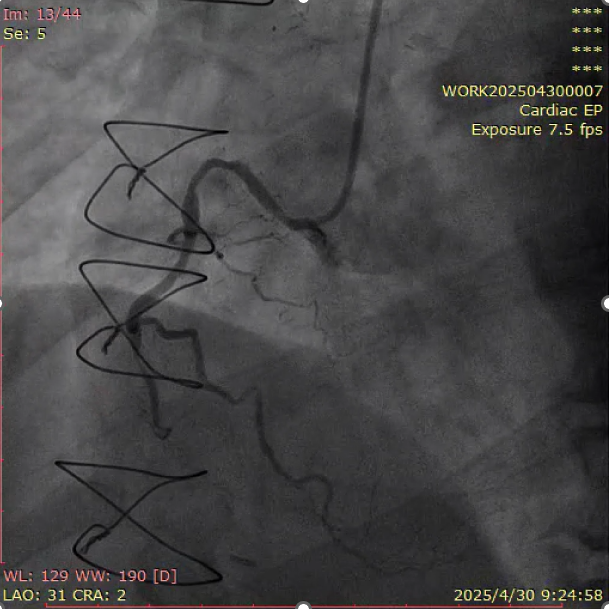

当地时间10月27日上午,大会“CHIP: CTOs Post CABG”论坛上,李闯医生代表团队分享了一例极具挑战性的逆向开通术病例(图9)。患者为冠脉搭桥术(CABG)术后5年再次发生急性心肌梗死,影像学提示供血静脉桥闭塞,团队决定通过桥血管作为逆向通路,尝试开通原生右冠状动脉(RCA)慢性闭塞病变(CTO)。

静脉桥闭塞是CABG术后患者急性心肌梗死的常见诱因,其特点为血栓负荷大、术中并发症风险高,且术后远期预后不理想。相较之下,重建原生血管的血运通道已被国际指南与专家广泛推崇。本例中,团队采用逐步推进的Tip-injection技术精准完成逆向路径建立,结合主动迎接技术(Active Greeting Technique, AGT)实现RCA CTO的顺利开通,最终获得良好临床效果(图10-11)。

图10.术前造影提示RCA-CTO

图11.RCA开通后血流恢复

术后讨论环节,与会专家围绕抗栓治疗策略、桥血管的后期管理及术中是否应联合使用左心室辅助装置等关键话题展开热烈交流。大会主席及多位国际嘉宾高度评价了病例的手术策略与处理流程,均认为其不仅体现了精湛的技术水平,也为类似复杂临床场景提供了宝贵的借鉴与启发。